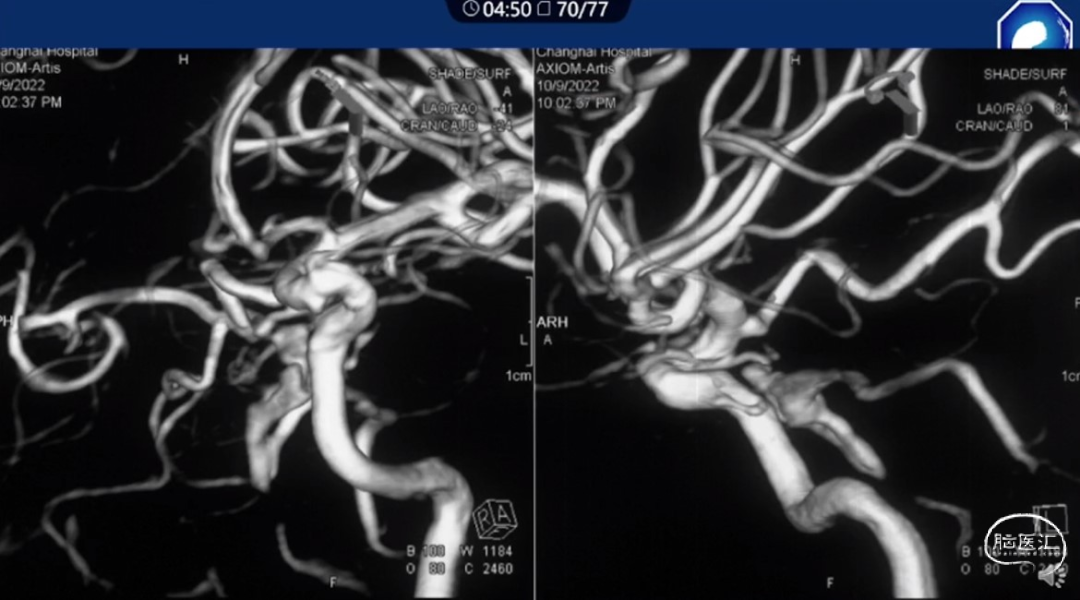

痿口静脉端的识别至关重要。

痿口静脉端精准完全闭塞是DAVF治愈的关键。

靶向性栓塞可以减少海绵窦分隔的过渡栓塞,有利于减少颅神经并发症,恢复海绵窦的正常引流功能。